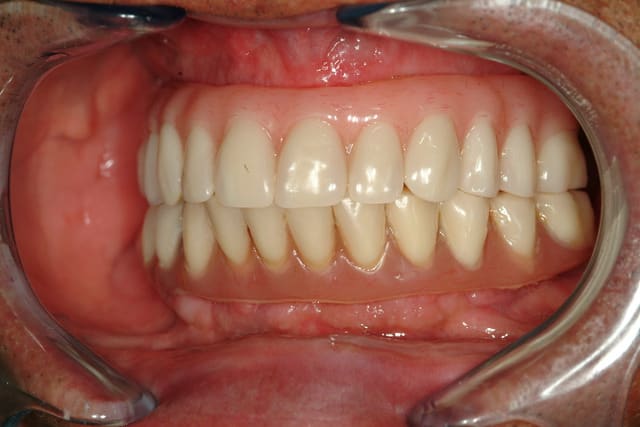

J'ai abandonné la MCI au maxillaire sur 4 implants c'est trop risqué.

Aucun filet de secours, je préfère avoir au moins 6 implants bloqués à min 30 Ncm, pour mettre en charge un maxillaire complet.

A la mandibule 4 implants, ça fonctionne très bien, j'en ai fait beaucoup aussi.

Voici déjà un cas avec 6 implants maxillaire et mandibulaire.

Le bas est pour le moment en résine, on doit passer plus tard à un bridge vissé sur armature métallique.

ce qui est primordial c'est d'avoir une crête la plus plate possible.

Il ne faut pas hésiter à faire des régularisation pendant la chirurgie.

En effet si la crête est plate, on peut demander au prothèsiste de faire l'intrados légèrement convexe.

De cette façon l'hygiène est facilitée.

Hydropulseur aussi vivement recommandé.